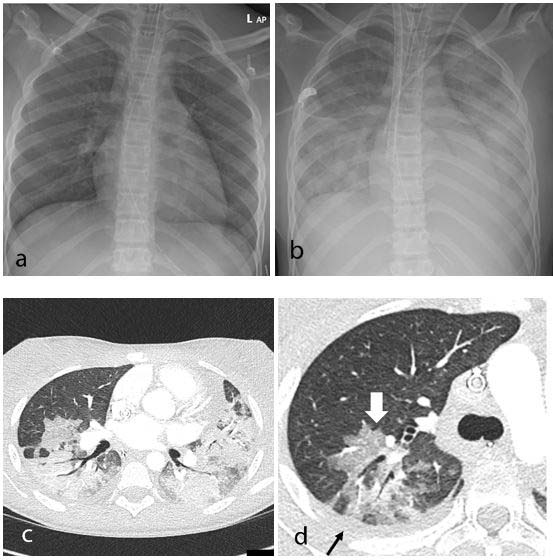

Thoracic findings in a 15-year-old girl with Multisystem Inflammatory Syndrome in Children (MIS-C). (a) Chest radiograph on admission shows mild perihilar bronchial wall cuffing. (b) Chest radiograph on the third day of admission demonstrates extensive airspace opacification with a mid and lower zone predominance. (c, d) Contrast-enhanced axial CT chest of the thorax at day 3 shows areas of ground-glass opacification (GGO) and dense airspace consolidation with air bronchograms. (c) This conformed to a mosaic pattern with a bronchocentric distribution to the GGO (white arrow, d) involving both central and peripheral lung parenchyma with pleural effusions (black small arrow, d).

The predominant findings on chest CT were basal consolidation and collapsed lung with pleural effusions. Abdominal ultrasound findings included inflammatory changes within the right iliac fossa, with mesenteric fat stranding, lymphadenopathy and bowel wall thickening, as well as free fluid in the pelvis.

All 35 children underwent chest X-ray due to fever, sepsis or features of multisystem inflammation. Nineteen X-rays were abnormal, the most common finding being that of bronchial wall thickening.

The study identified a pattern of imaging findings in post COVID-19 MIS-C, including airway inflammation, rapidly progressive pulmonary edema, coronary artery aneurysms and extensive abdominal inflammatory changes within the right iliac fossa.